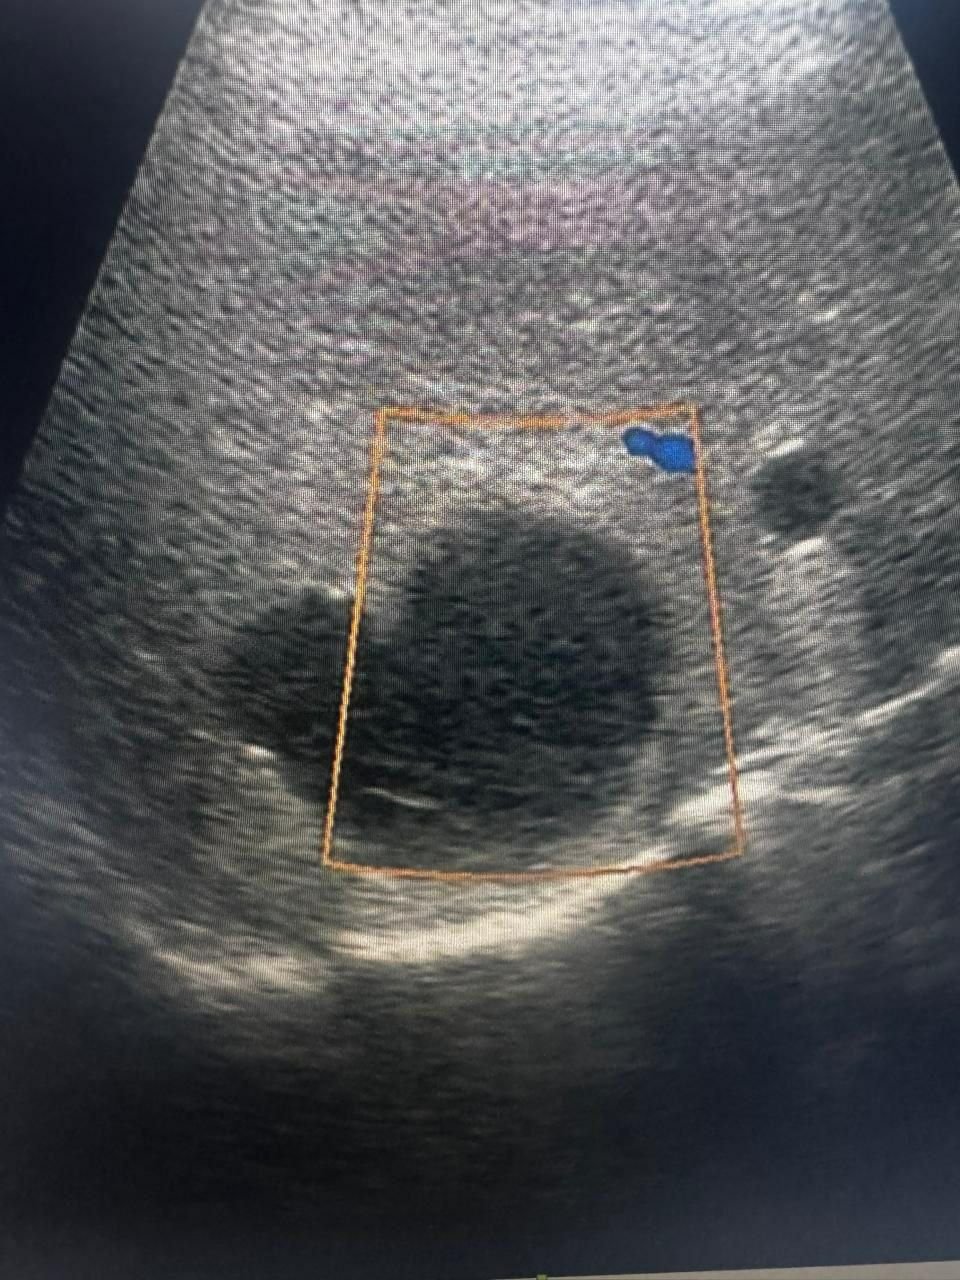

PrimaMedia, 26 ноября. Жителя Приморья экстренно доставили в больницу Владивостока с острой болью, где врачи обнаружили у него кисту размером с целый орган. Хирургам удалось спасти 53-летнего пациента и избежать сложной полостной операции, сообщила пресс-служба Минздрава Приморья.

"Под местной анестезией, под контролем УЗИ мы выбрали оптимальную точку доступа, установили дренаж и эвакуировали около двух литров жидкости из кисты. Затем ввели склерозирующие препараты — они позволяют “склеить” полость и избежать повторного заполнения", — приводит пресс-служба слова руководителя отделения общей хирургии Игоря Кондрашова.